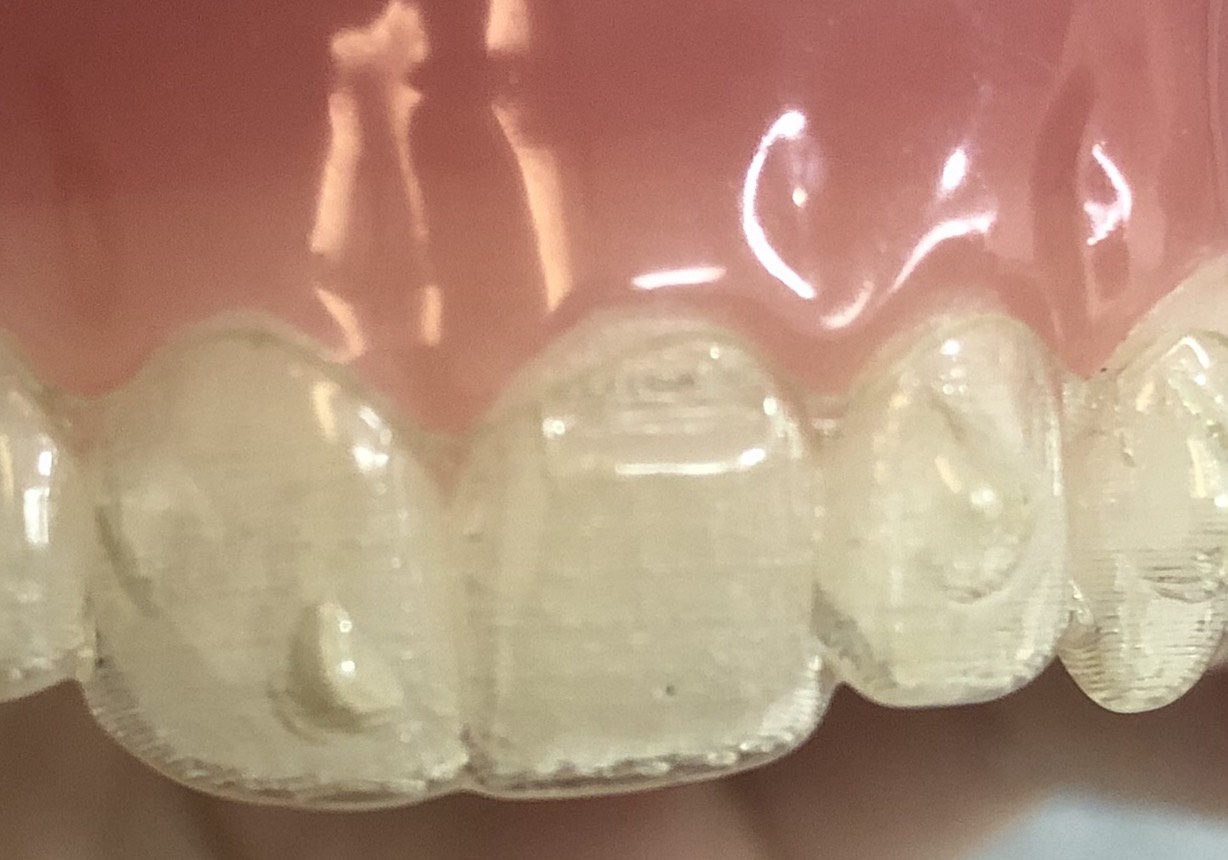

歯にアタッチメントという材料を付けていきます。

どこにアタッチメントが付いているか分りますか?

実は3本の歯全てに付いています。